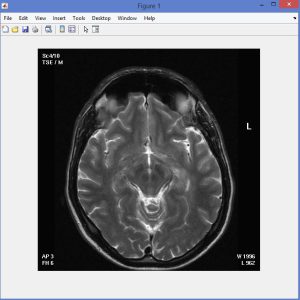

Fuzzy C-Means with Spatial constraint